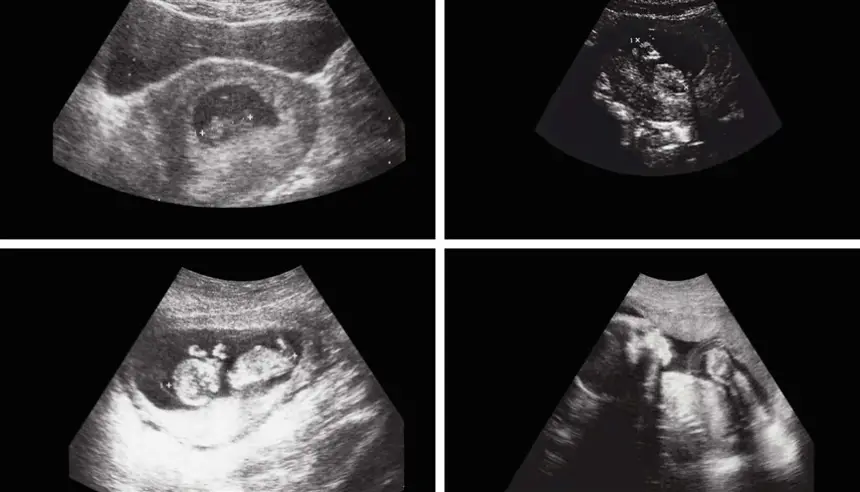

وبحسب صحيفة Need To Know، استقبل المستشفى الرضيع وهو يعاني من انتفاخ غير طبيعي في البطن، ما دفع الأطباء إلى الاشتباه في وجود ورم كلوي. لكن الفحوصات الدقيقة بالأشعة كشفت عن وجود تكوين داخل البطن يحتوي على أنسجة رخوة ودهون وسوائل، بالإضافة إلى بنية عظمية واضحة، ما أثار شكوك الفريق الطبي بوجود جنين داخل جسد الرضيع.

وأجرى الجراحون عملية استغرقت عدة ساعات، تمكنوا خلالها من استخراج الجنين، الذي بلغ حجمه نحو 8×12 سنتيمتراً. وأكد الأطباء أن هذه الحالة النادرة تُعرف طبياً باسم "الجنين داخل الجنين"، وتحدث نتيجة اضطراب نادر في مراحل الحمل الأولى.